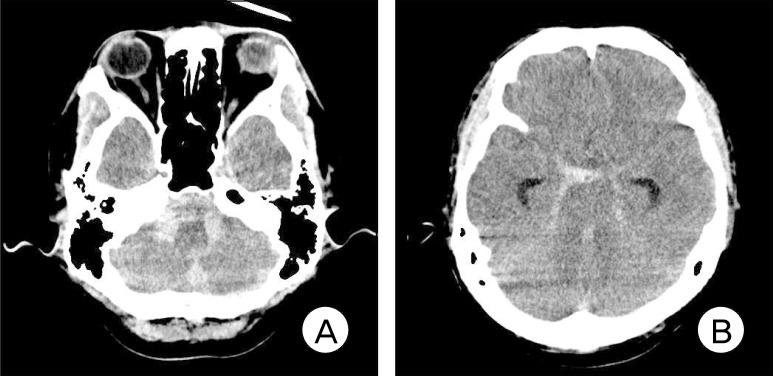

Incidence of aneurysm of the anterior spinal artery is known to be very low and the standard treatment strategy has not yet been established. The author experienced a case of subarachnoid hemorrhage (SAH) caused by the rupture of an aneurysm in the branch of the cervical anterior spinal artery, which was managed conservatively. The patient had end-stage common bile duct cancer and survived for 103 days after onset of the SAH without a re-rupture of the aneurysm.

已知脊髓前动脉动脉瘤的发病率非常低,且尚未确立标准的治疗策略。作者遇到一例由颈段脊髓前动脉分支处动脉瘤破裂引起的蛛网膜下腔出血(SAH)病例,该病例采用保守治疗。患者患有终末期胆总管癌,蛛网膜下腔出血发病后存活了103天,动脉瘤未再次破裂。